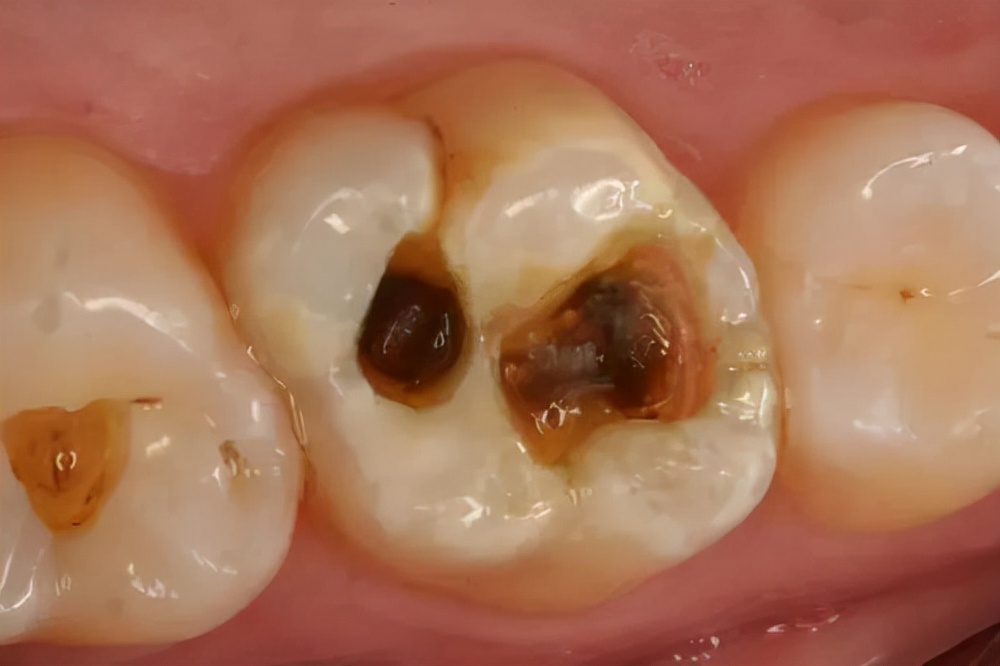

我们都知道,牙齿表面存在一些 深的窝沟 ——

如图所示,难以清洁的窝沟

这些部位通常 难以清洁 ,食物残渣和细菌容易堆积, 是蛀牙的好发部位。